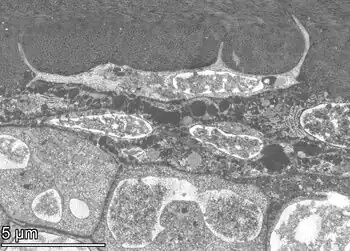

![]() Transverse section of a bone | |

Osteocytes have a stellate shape, approximately 7 micrometers deep and wide by 15 micrometers in length.[3] The cell body varies in size from 5–20 micrometers in diameter and contain 40–60 cell processes per cell,[4] with a cell to cell distance between 20–30 micrometers.[3] A mature osteocyte contains a single nucleus that is located toward the vascular side and has one or two nucleoli and a membrane.[5] The cell also exhibits a reduced size endoplasmic reticulum, Golgi apparatus and mitochondria, and cell processes that radiate largely towards the bone surfaces in circumferential lamellae, or towards a haversian canal and outer cement line typical of osteons in concentric lamellar bone.[5] Osteocytes form an extensive lacunocanalicular network within the mineralized collagen type I matrix, with cell bodies residing within lacunae, and cell/dendritic processes within channels called canaliculi.[6]